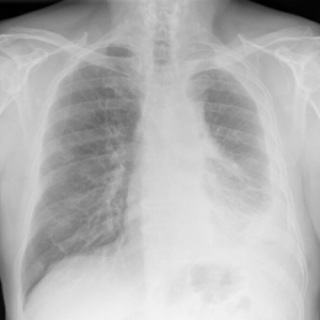

What Does Mesothelioma Look Like on an X-Ray?

Digital chest x-ray of advanced malignant mesothelioma on left.

On a chest X-ray, pleural or pericardial mesothelioma tumors appear as wispy white areas around the lungs, while calcified tumors appear bright white. Bones appear white and healthy lungs are dark. Most abnormalities appear as lighter areas that are hazy or solid.

Tumors and scarring may distort chest anatomy. Compressed lungs or a raised diaphragm can be visible on an X-ray.

X-rays are 2D, making it hard to determine if a tumor is in the lung, pleura or the mediastinum around the heart. Additionally, X-rays don’t clearly show peritoneal or testicular mesothelioma. CT, MRI and PET/CT scans offer more detailed images for all mesothelioma types.